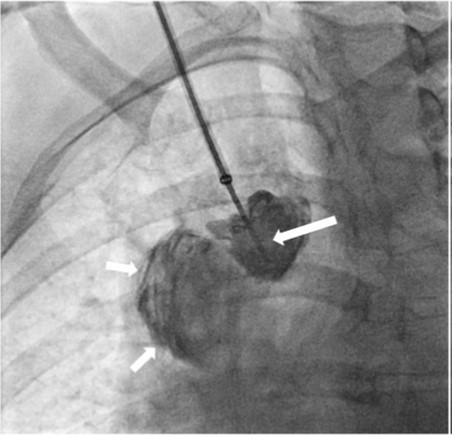

Fig. 1.

Fig 1. Venogram shows occlusion of the right brachiocephalic vein with multiple collaterals in the right neck.

우측 중심정맥조영술에서 우측 상완두정맥(brachiocephalic vein)이 완전히 막혀있고 경정맥으로 여러 개의 측부혈관(collateral vessel)들이 관찰됨

초음파 유도 하에 우측 팔의 동정맥루 graft를 천자한 후 정맥조영술을 시행하여 우측 상완두정맥의 폐색을 확인함(Fig. 1). 5Fr Cobra 카테터(Cook, Bloomington, IN, USA)와 친수성 0.035 inch 유도철사(Terumo, Tokyo, Japan)로 폐색부위의 통과를 시도하였으나 실패함. 우측 대퇴정맥을 천자하고9Fr 65cm sheath (Arrow, Deutschland, Erding, Germany)를 상대정맥까지 진입시킨 후 5Fr Davis 카테터를 통해 약 2cm 길이의 상완두정맥 폐색 부위를 확인함(Fig. 2). Davis 카테터와유도철사로 상대정맥에서 우측 상완두정맥으로 통과를 시도함. 유도철사의 soft tip 부분으로 시도하였을 때 통과가 되지 않아서 반대쪽 hard tip 부분으로도 통과를 시도 하였으나 실패함(Fig.3). 유도 철사의 soft tip 과 hard tip 양쪽 모두 사용 하여 통과를 시도하였으나 막힌 부위의 위쪽 부분은 앞쪽(anterior side of the body) 을 향하고 있고 아래쪽 부분은 뒤쪽(posterior side of the body)를 향하고 있어서 천자 방향을 맞추기 어려웠음(Fig. 3). 우측 내경정맥을 천자하고 5Fr sheath를 삽입함. Sheath를 통해서 5FrKumpe 카테터와 0.035 inch 유도철사로 위에서 아래 방향으로 폐색부위 통과를 시도함. Hard tip으로 시술 도중 폐색혈관 주위로 유도 철사가 천자되어서 조영제의 누출이 있었으나 천자부위 주에 국한되어 있었고 임상적으로 문제 있는 혈류역학적 변화는 오지 않았음. Kumpe 카테터와 유도철사로는 천자 방향을 맞추기가 어려워서TIPS set (Cook, Bjaeverskov, Denmark)를 사용하기로 함. 천자된내 경정맥에 10Fr introducer sheath를 삽입하고 20G Colapinto needle을 폐색부위까지 진입시킴. 양쪽에서 정맥 조영술을 시행하여 폐색된 부위의 위치와 길이를 여러 각도에서 정확히 파악한 후, 폐색 부위를 천자함(Fig. 4). 천자 후 Colapinto needle을 통해 유도철사를 상대정맥에 진입시킴. 대퇴동맥을 통하여 삽입된 snare 카테터(ev3, Plymouth, MA, USA)를 이용하여 대퇴정맥 밖으로 유도철사를 빼냄(through and through technique)(Fig 5). 유도 철사만 통과된 상태에서 천자부 주위에 여러번의 천자로 인한 조영제 누출이 있었으나 주출된 조영제의 양이 적었으며 천자부 주위에 국한되어 있었음. Tractogram시행시 조영제의 누출은 보이지 않아서 유도 철사 주위에 국한 되어 있어서 풍선확장술을 시행 하기로 함(Fig. 6).대퇴 정맥을 통해 유도철사를 0.035 inch Amplatz wire(Cook, Bjaeverskov, Denmark)로 교체하여 내경정맥까지 진입시킨 후 풍선카테터 (Bard, NJ, US)를 삽입함.천자된 통로를 따라 직경 6 mm에서부터 16 mm까지의 풍선카테터로 차례대로 풍선확장술을 시행함(Fig. 7). 시술 후 정맥조영술에서 폐색부위는 개통되어 원활한 혈류를 보였음(Fig. 8). 시술 후에 오른쪽 팔의 종창은 호전됨.